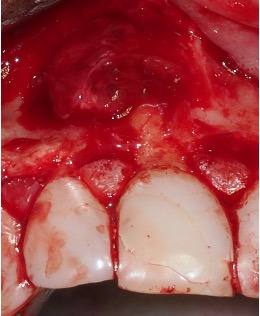

Apical surgery

In cases where non-surgical root canal treatment has failed apical surgery may be indicated. Often there is a cyst that requires enucleation around the end of the root. Then the root tip is removed and the end of the root sealed with a retrograde root filling. In large lesions a general anaesthetic may be required. The tissue may also require sending off for a biopsy.